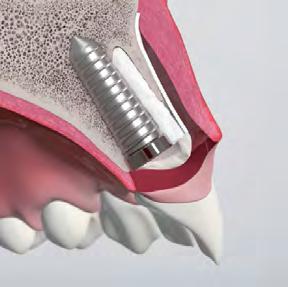

3D implant placement (using a surgical guide)

• Good bone availability for palatal wall implant positioning

Use of a narrow or regular diameter implant

• Achieve primary stability and maintain a buccal gap >2 mm